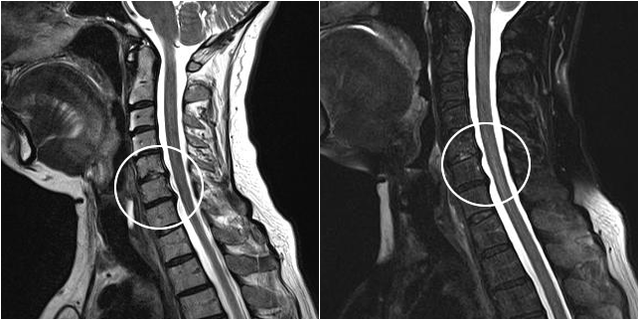

Suvremene dijagnostičke metode uključuju MRI i CT, koji omogućuju najpreciznije ispitivanje procesa uništavanja hrskavice i koštanog tkiva. Također, pomoću ove tehnike pogodno je dijagnosticirati kile i druge defekte mekog tkiva u blizini izvora bolesti.